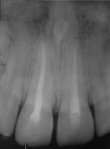

Diagnostic assessment: the teeth were dislocated at a one-millimeter palatal version. Both maxillary central incisors were sensitive to percussion and exhibited class I tooth mobility. A periapical radiograph revealed that both incisors had closed apices, and no root or bone fractures were detected (Figure 2). We observed an increase in periodontal ligament space.

Figure 2: re-operative radiograph